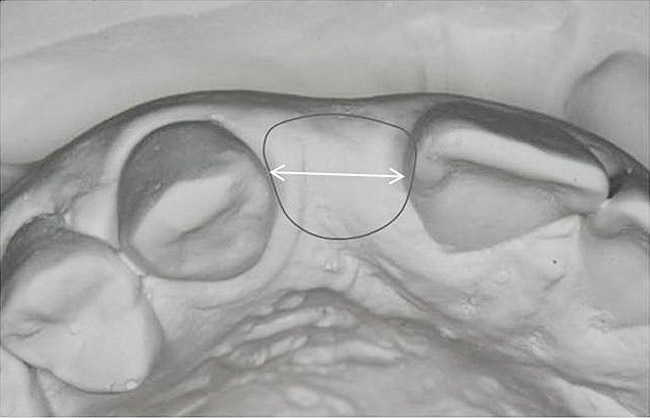

Figure 13   Exploiting study casts for planning single-tooth implant placement and restoration: Mounted study casts permit an estimation of available bone volume (Fig 13); measure the bound edentulous space inter-tooth dimensions (Fig 14); measure the available inter-arch dimension (restorative space) (Fig 15); and evaluate alveolar ridge/tooth relationships (distance from zenith represented by plastic stent to ridge crest) (Fig 16).

Figure 13

Figure 14   Exploiting study casts for planning single-tooth implant placement and restoration: Mounted study casts permit an estimation of available bone volume (Fig 13); measure the bound edentulous space inter-tooth dimensions (Fig 14); measure the available inter-arch dimension (restorative space) (Fig 15); and evaluate alveolar ridge/tooth relationships (distance from zenith represented by plastic stent to ridge crest) (Fig 16).

Figure 14

Figure 15  Exploiting study casts for planning single-tooth implant placement and restoration: Mounted study casts permit an estimation of available bone volume (Fig 13); measure the bound edentulous space inter-tooth dimensions (Fig 14); measure the available inter-arch dimension (restorative space) (Fig 15); and evaluate alveolar ridge/tooth relationships (distance from zenith represented by plastic stent to ridge crest) (Fig 16).

Figure 15

Figure 16  Exploiting study casts for planning single-tooth implant placement and restoration: Mounted study casts permit an estimation of available bone volume (Fig 13); measure the bound edentulous space inter-tooth dimensions (Fig 14); measure the available inter-arch dimension (restorative space) (Fig 15); and evaluate alveolar ridge/tooth relationships (distance from zenith represented by plastic stent to ridge crest) (Fig 16).

Figure 16